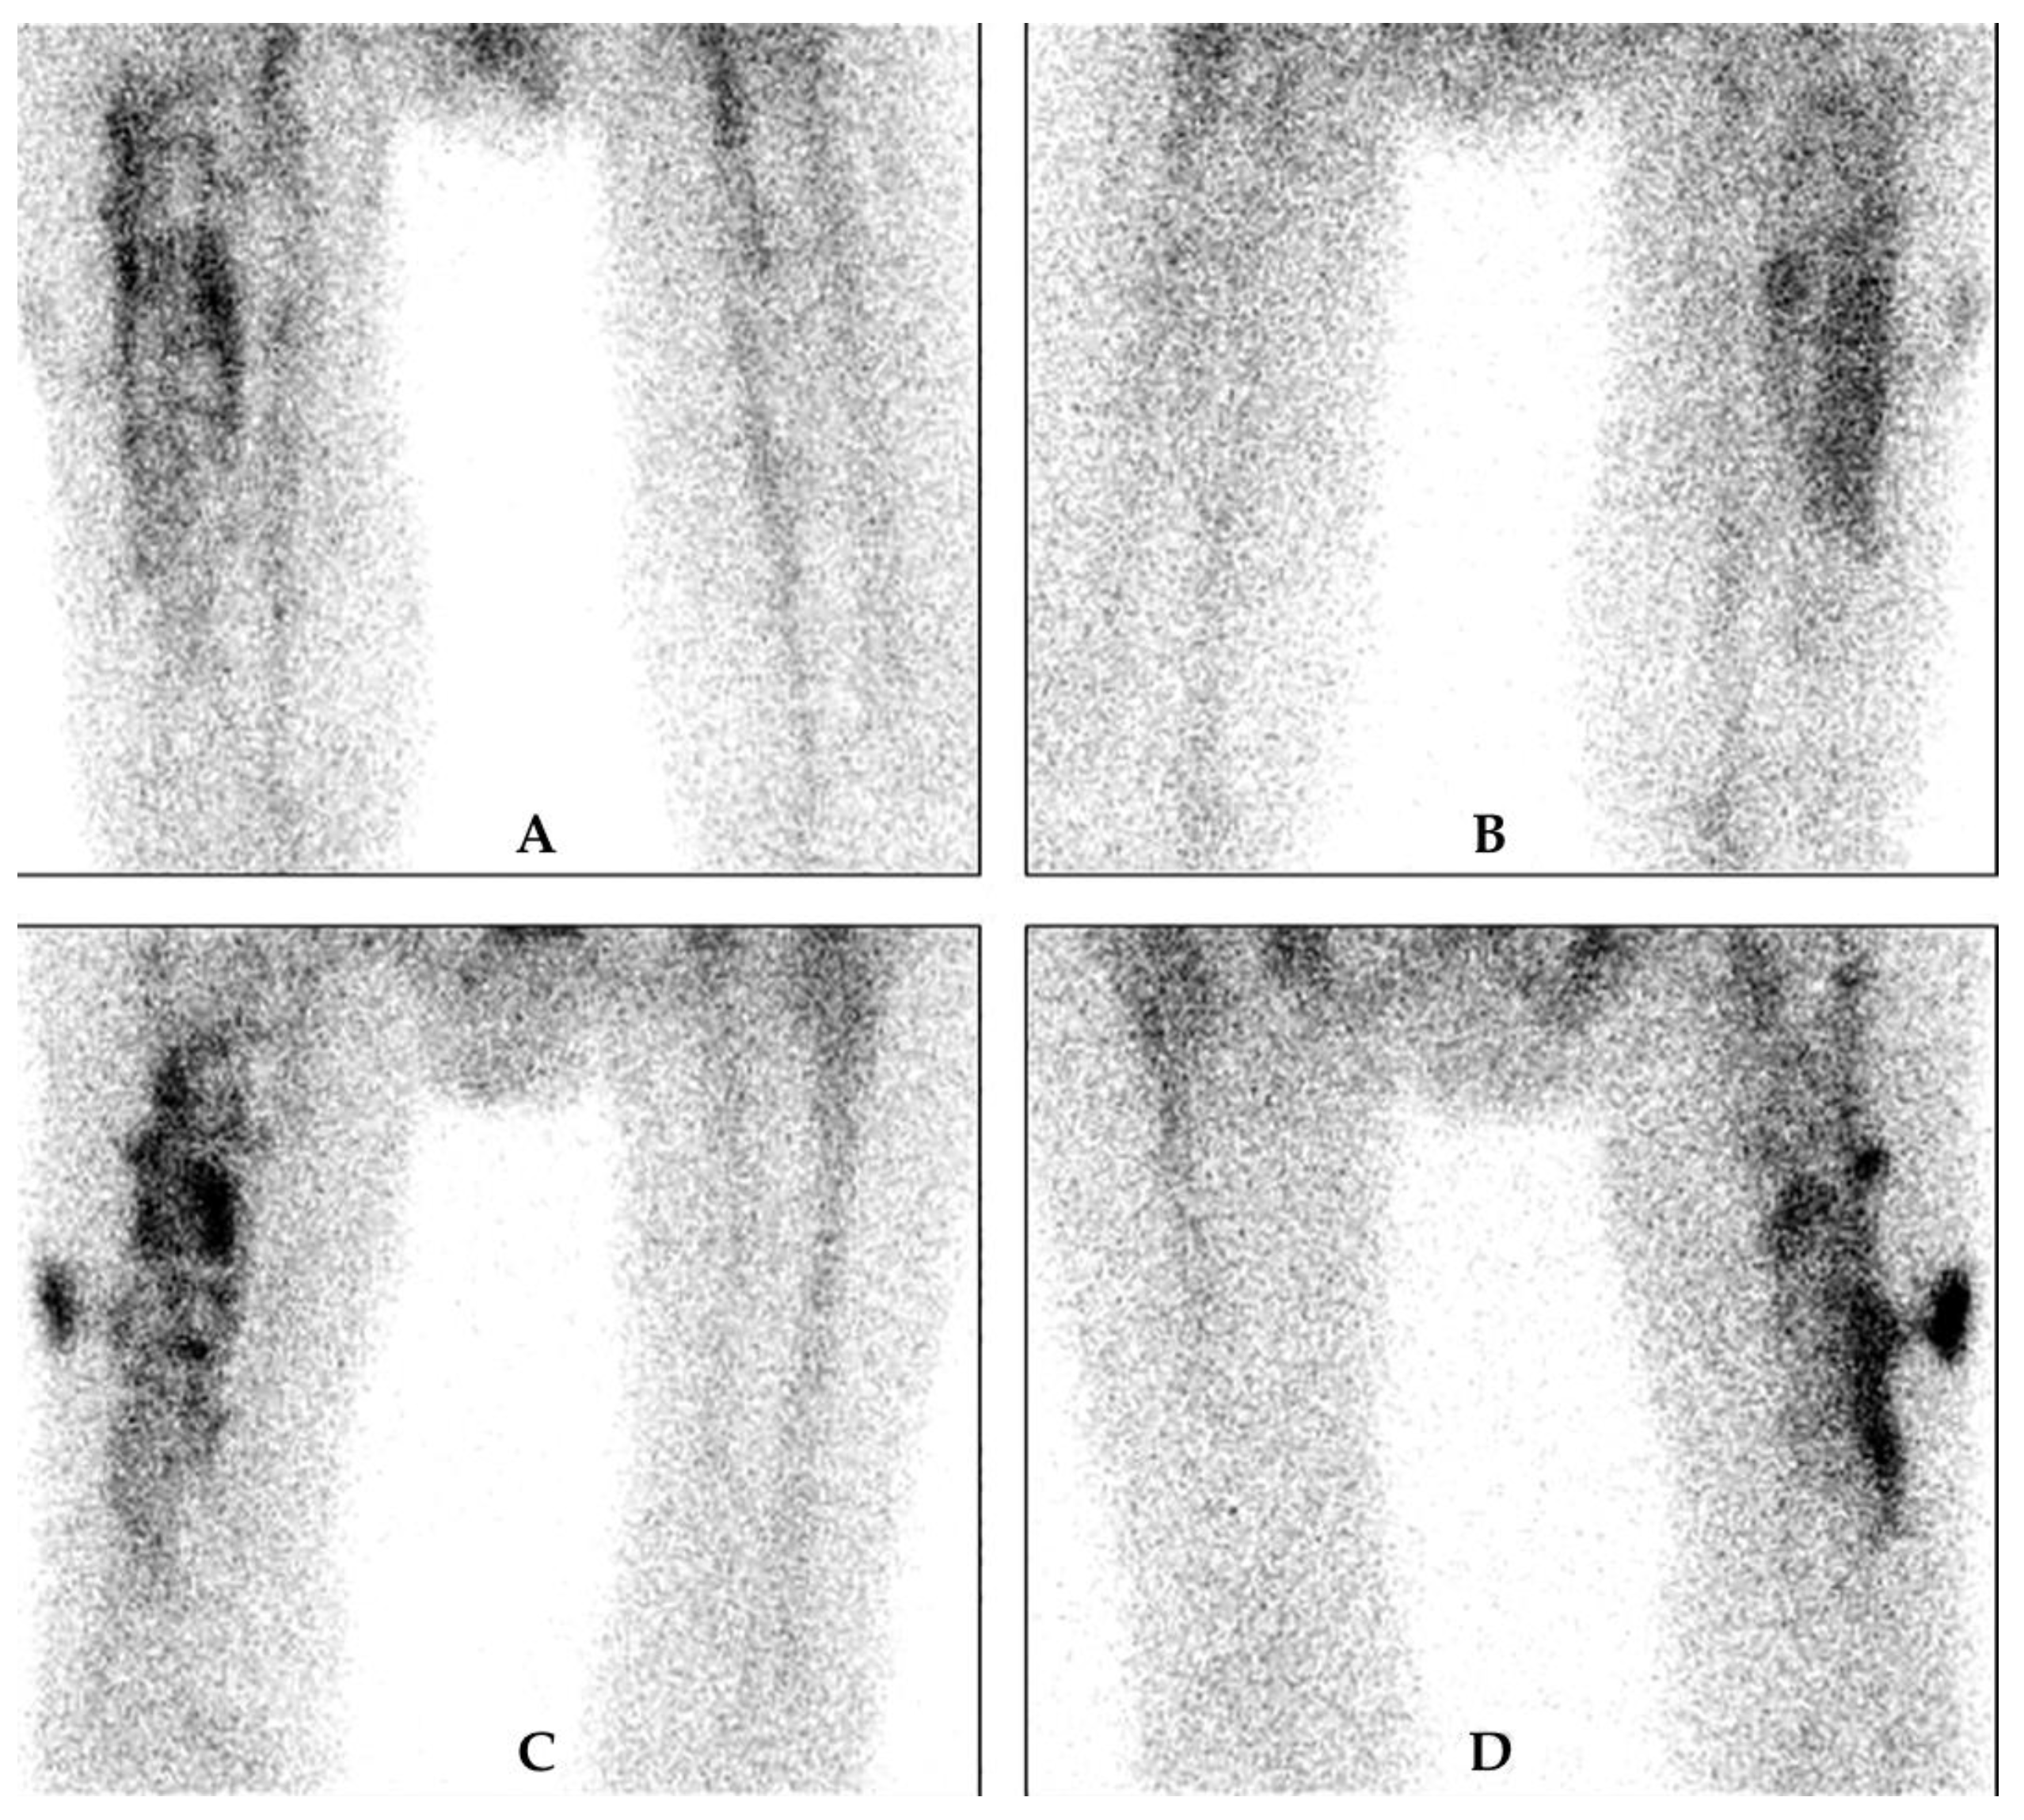

4.2. White Blood Cell Scintigraphy

5.6. What Is the Minimum Time Window between the Date of Surgery and a Three-Phase Bone Scan to Diagnose a PJI?

5.7. What Is the Role of a WBC Scan to Diagnose a PJI (Is a Negative Scan Sufficient to Exclude a PJI)?